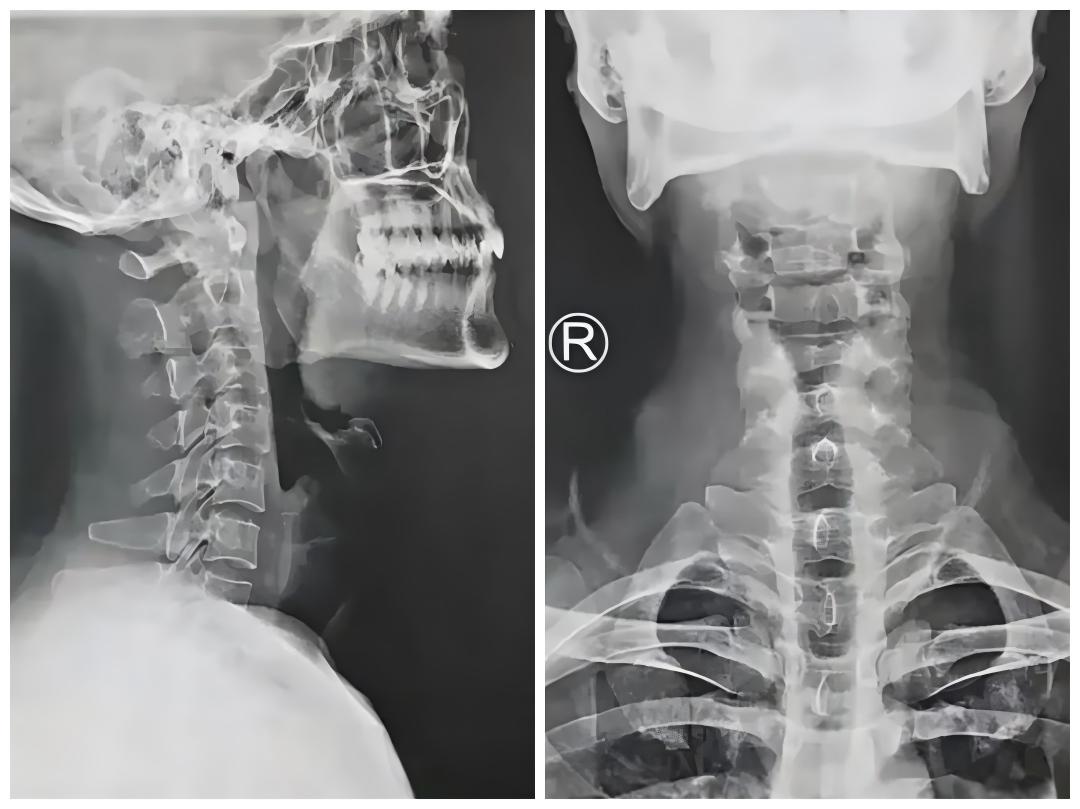

颈椎X线、CT、磁共振成像(MRI) 等影像学检查结果多为阴性,部分患者可观察到颈椎曲度改变、骨质增生等。